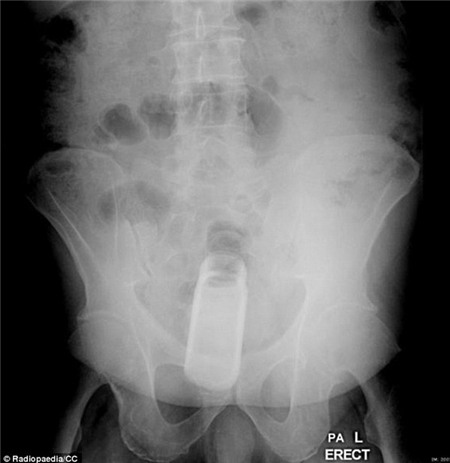

Trong

khi đó, một bệnh nhân khác thậm chí còn có một hộp café của một hãng

nổi tiếng trong người. Hộp café này vẫn còn nguyên nắp cao su.